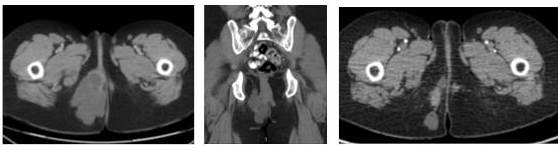

Una nueva tomografía (marzo 2020) muestra dos lesiones densas de 3,5 cm irregulares dominantes, una en el subcutáneo entre periné y el glúteo derecho y la otra en plano profundo de la fosa isquiorrectal que compromete el labio mayor derecho de la vulva, unidas por área densa heterogénea con cambios posquirúrgicos que en conjunto mide 9,6 cm x 7,8 cm, sin compromiso óseo. Se realiza RMN para precisar compromiso de tejidos blandos y descartar infiltración ano rectal. Se observa, además, la adenopatía inguinal derecha, sin criterios de sospecha.